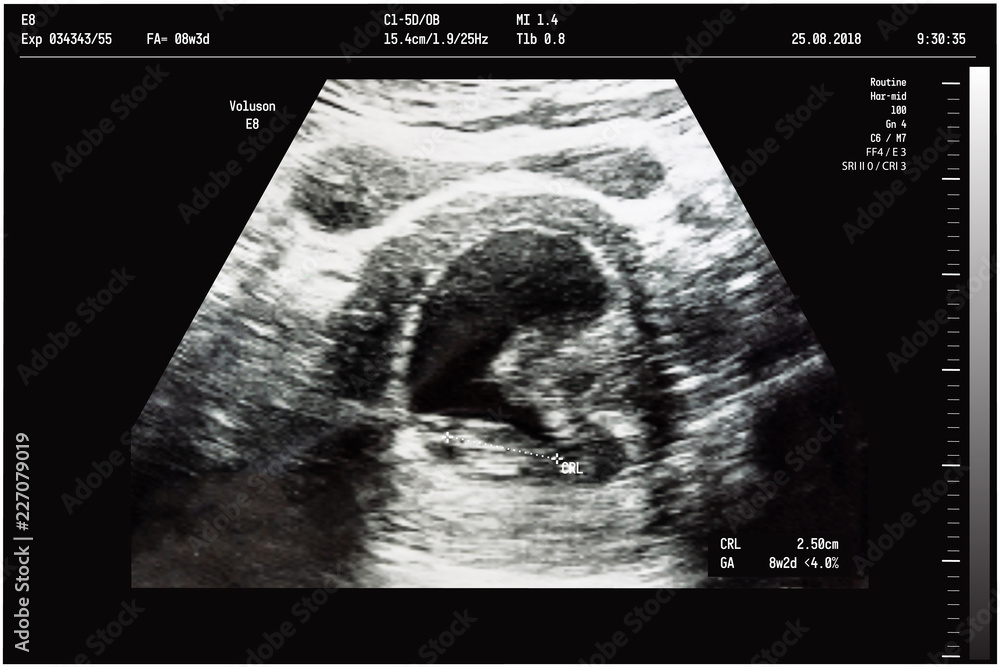

Baby Ultrasound: What Should I Be Expecting During Visits

pandagossips.comultrasound baby video womb pregnancy stock hd body birth shutterstock videoblocks month footage pregnant amish women during mother expecting third

pandagossips.comultrasound baby video womb pregnancy stock hd body birth shutterstock videoblocks month footage pregnant amish women during mother expecting third

animalia-life.clubAn Ultrasound Of A Mother Fetus During The 08th Week Background As

animalia-life.clubAn Ultrasound Of A Mother Fetus During The 08th Week Background As

stock.adobe.comUltrasound HD Wallpaper | Pxfuel

stock.adobe.comUltrasound HD Wallpaper | Pxfuel

designbundles.netWhen And Why To Get Ultrasounds During Pregnancy - The New York Times

designbundles.netWhen And Why To Get Ultrasounds During Pregnancy - The New York Times

www.nytimes.comultrasounds ultrasound

www.nytimes.comultrasounds ultrasound